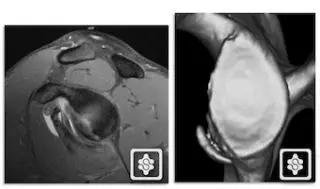

Hill-Sachs 损伤的 MR 片(来源:Hill-Sachs Injuries of the Shoulder)

MRI 示反 Hill-Sachs 损伤程度 (来源:Anatomical Reconstruction of Reverse Hill-Sachs Lesions Using the Underpinning Technique. Orthopedics May 2012 - Volume 35 · Issue 5: e752-e757)